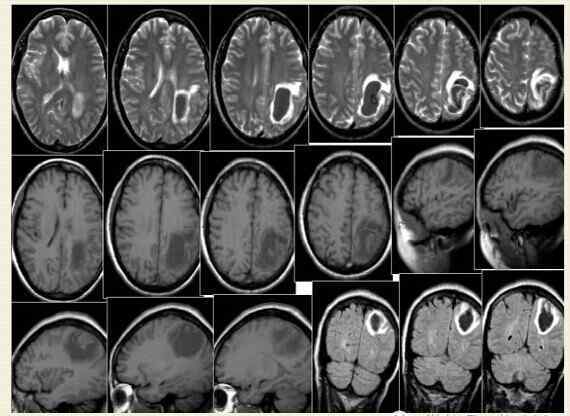

高血压脑出血是指非创伤性脑实质自发性出血,多见于50岁以上的高血压动脉硬化患者。主要原因是与高血压相关的动脉病,常见于壳核、外囊、丘脑、内囊和大脑半球白质(见下图)

皮质动脉穿支-脑叶出血

纹状体外侧动脉-壳核出血

丘脑穿通动脉-丘脑出血

桥旁动脉出血

小脑出血(齿状核),小脑出血和AICA的一个分支

随着出血量的增加,形成血肿,脑组织被破坏,血肿及其周围脑组织水肿、受压。脑内血肿在不同时期有不同的病理改变,相应出现不同的影像学改变。

1.超急性期(6小时内):血肿内红细胞完整,主要含氧合血红蛋白。

2.急性期(7-72小时):红细胞脱水萎缩,主要含脱氧血红蛋白。此期病灶周围水肿,占位效应明显。

3.亚急性期(3天-2周):红细胞以铁血红蛋白为主,水肿和占位效应减轻。

4.慢性期(2周后):水肿消失,含铁血黄素演变成含铁血黄素,血肿小到足以填满,但大到足以留下囊腔。

急性脑出血在CT上定位准确,是高密度图像。